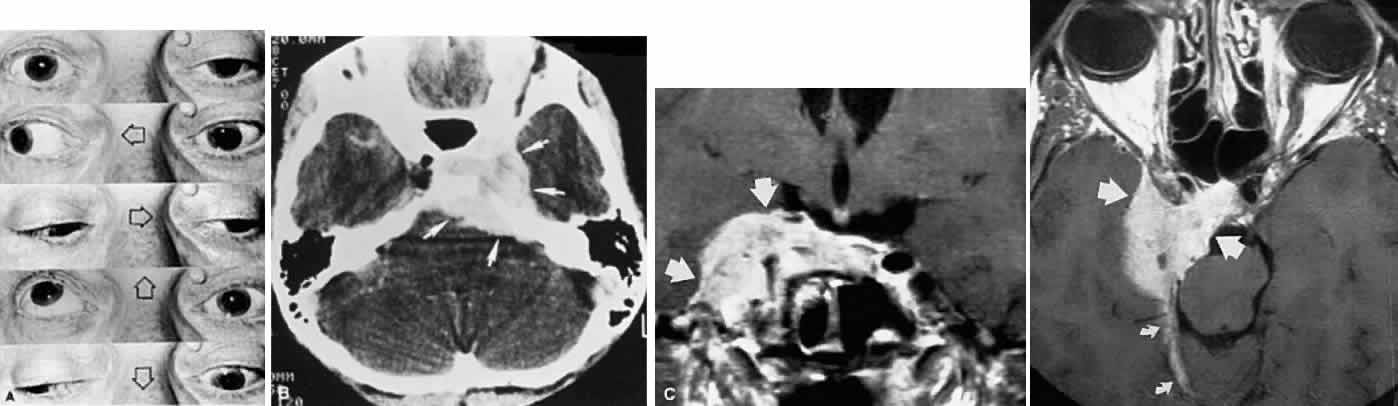

Acquired bi-nuclear total ophthalmoplegia is occasionally seen (Fig. 11), as reported by Masucci.82 These findings are the result of thrombotic or embolic processes at the level of the basilar bifurcation, with occlusion of the median mesencephalic perforating arteries. Congenital bilateral total ophthalmoplegia with or without levator and pupil sparing has been reported and may be associated with dysplasia of the corpus callosum.83

Fig. 11. Bilateral oculomotor palsies (nuclear?) associated with abrupt onset of vertigo and mild left hemiparesis.

The bulbar variant of the Guillain-Barré syndrome (Landry ascending paralysis) often presents as a painless, rapidly progressive bilateral ophthalmoplegia. As it evolves, this cranial polyneuropathy may mimic unilateral or bilateral oculomotor palsies, but it usually progresses to a more or less total symmetric ophthalmoplegia that may include the pupils and accommodation. Lid elevators can be normal or minimally involved. The presence of acute or subacute facial diplegia confirms the diagnosis and practically excludes other considerations (Fig. 17).

Commonly, the disorder follows a febrile or “viral” illnesses, or is seen in association with infectious mononucleosis. Although the well-known cerebrospinal fluid protein elevation, in the absence of cellular response, is a sine qua non of this disorder, by no means is this dissociation a constant finding. Detailed nerve conduction studies in one patient with generalized Guillain-Barré syndrome129 revealed that demyelination occurred first in the most distal nerve and progressed to the spinal root; during recovery, remyelination occurred initially at the spinal root level. This sequence may explain the typical interval of days to weeks between onset of symptoms and rise in cerebrospinal fluid protein, which probably increases only when the spinal roots become involved.

In 1956, Fisher130 documented the ophthalmoplegic variant of acute idiopathic polyneuritis, characterized by oculomotor palsies, areflexia, and ataxia. Pathologic material published by Asbury et al131 demonstrated inflammatory infiltration of nerve roots, including peripheral and cranial nerves; these authors proposed that their findings suggest that the polyneuritis syndrome is related to a lymphocyte-mediated autoimmune reaction. The patient studied by Grunnet and Lubow,132 however, showed central chromatolysis in the nuclei of the third, fourth, fifth, and twelfth nerves, and of the anterior horn cells, with only sparse lymphocytic infiltration. Additional clinical evidence that Fisher's syndrome can indeed affect the central nervous system (CNS) includes the following: loss of voluntary saccades with preservation of pursuit; upgaze paresis with intact Bell's phenomenon; internuclear ophthalmoplegia; cerebellar ataxia; hemiparesis; extrapyramidal signs; and disorders of consciousness, including obtundation and electroencephalographic abnormalities.133 Radiologic abnormalities include enhancing midbrain tegmental lesions in a case of bilateral internuclear ophthalmoplegia, vertical gaze palsy, ataxia, and hyporeflexia.134